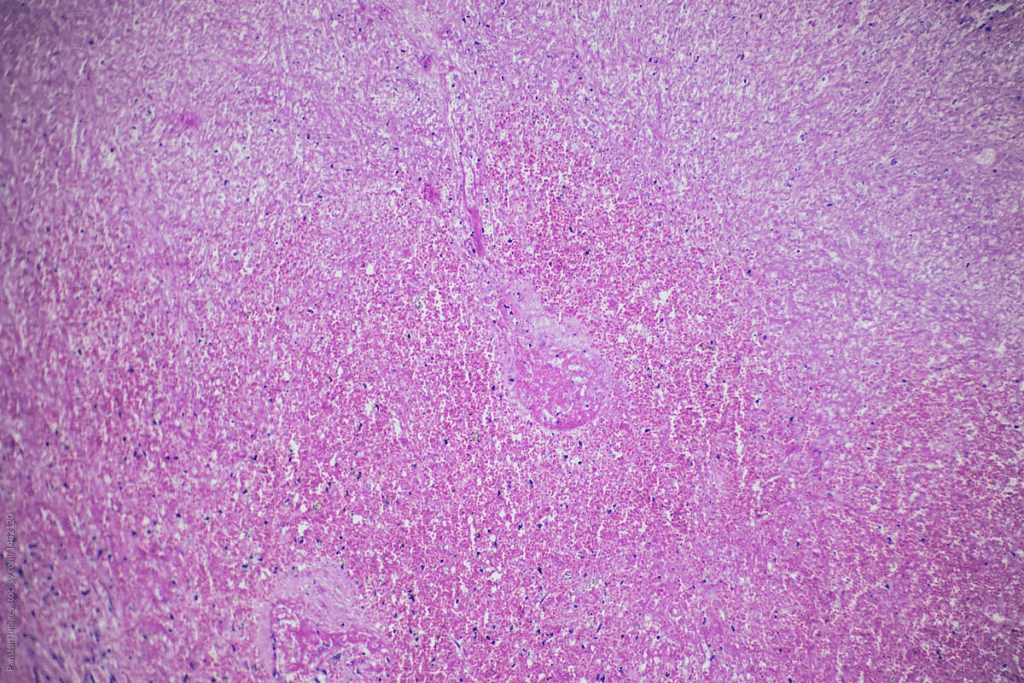

The posterior pituitary mainly has pituicytes, which are glial cells. These cells support the axons from the hypothalamus. They are vital for hormone storage and release.

Herring Bodies and Neurosecretory Structures

Herring bodies are found in the posterior pituitary. They are swellings where hormones are stored before being released. This shows the gland’s role in hormone storage and release.